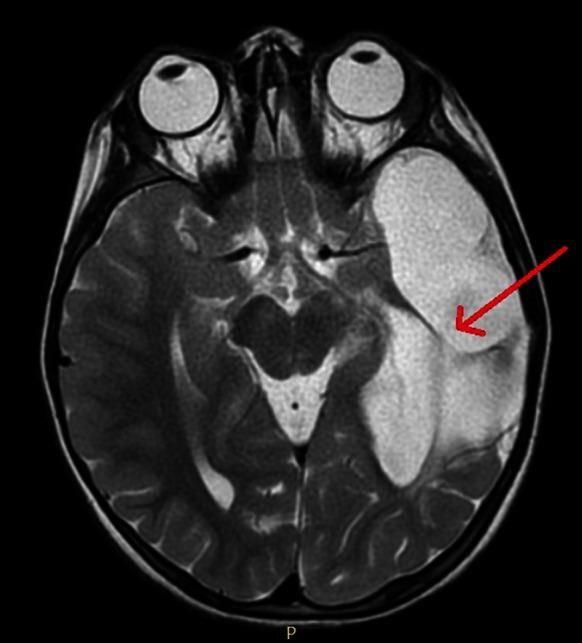

At baseline, abnormalities were found in the right eye: exotropia and lack of foveal fixation. Visual acuity was not achieved. Pupillary responses were normal in both eyes. There was no evidence of nystagmus. Flash visual evoked potentials were normal and equal in both eyes. When repeated one year later the signal had deteriorated in both eyes; the peak times of N2 and P2 had increased. The increased VEP latencies were the only ocular signs noted. After referral to neurosurgery, intracranial hypertension was found and a shunt was performed.

基线时,右眼发现异常:外斜视和中央凹注视缺失。未达到视力。双眼瞳孔反应正常。无眼球震颤证据。双眼闪光视觉诱发电位正常且相等。一年后复查时,双眼信号均变差;N2和P2的峰值时间增加。VEP潜伏期增加是唯一观察到的眼部体征。转诊至神经外科后,发现颅内高压并进行了分流手术。